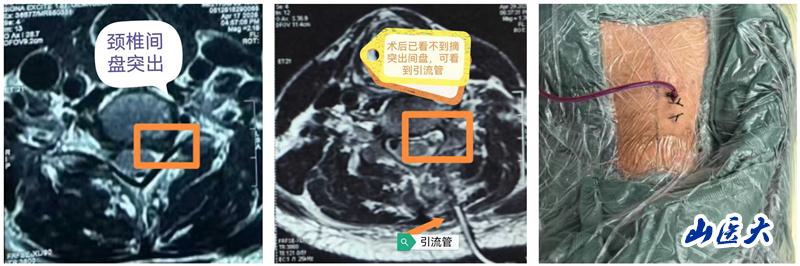

近日,万象城第二医院骨科脊柱二病区王少伟教授团队成功为一例神经根型颈椎病患者实施了单侧双通道内镜下的颈椎Keyhole(俗称“钥匙孔”)微创手术。手术全程顺利,术中精准解除患者神经压迫,术后患者左上肢疼痛即刻解除,术后第二天便可下床正常行走。

颈椎Keyhole微创手术是指在椎板上开设一个如钥匙孔般精细的通道,通过脊柱内镜技术完成病灶清除与神经减压。该术式不仅最大程度地保留正常解剖结构,还能有效缓解神经根压迫,为颈椎疾病患者带来更加舒适的治疗体验和更快的康复进程。近年来,随着脊柱内镜技术的迅猛发展,单侧双通道内镜技术在腰椎疾病的治疗中得到了广泛应用,如今,这项先进技术正逐步延伸至颈椎领域,开启了颈椎治疗的全新篇章。作为一项突破性的微创治疗手段,Keyhole入路为神经根型颈椎病的手术治疗提供了更安全、更精准、更高效的解决方案。